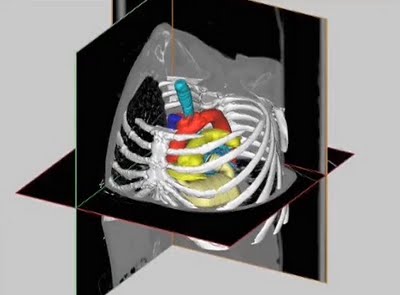

We ran across an interesting video that talks about Materialise’s ventures into the medical manufacturing space. We’ve posted about medical uses of 3D print tech before, but Materialise specializes in this niche, and have for quite some time. Materialise produces 3D software specifically designed for this market: Mimics, which can transform medical 2D CT or… Continue reading Biomedical Solutions Materialise